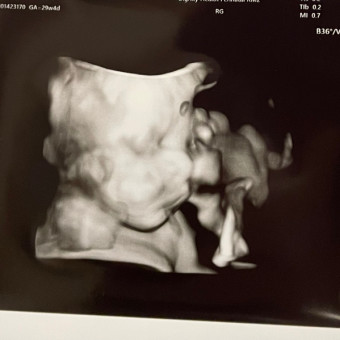

Archer Rhodes

Hilary & Courtney Wickman

May 2026